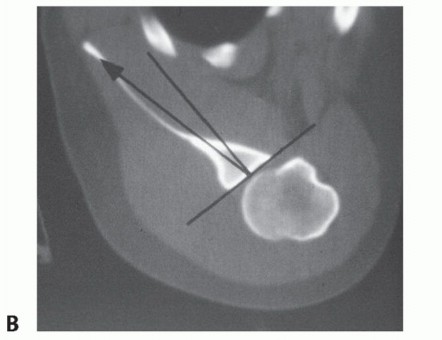

FIG 2 • A. Axillary radiograph of patient with voluntary posterior instability, reproducing the instability while taking the radiograph. B. CT scan demonstrating significant posterior glenoid retroversion in a patient with posterior instability.

A computed tomography (CT) scan can be helpful to evaluate humeral head defects and associated fractures of the tuberosities, humeral shaft, and posterior glenoid rim. Significant posterior glenoid

retroversion can also be demonstrated on CT scanning (FIG 2B*).